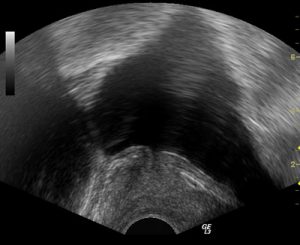

Prostat vəzinin adenomasının diaqnozun qoyulması kifayət qədər asandır. Artıq ilkin tanışlıq zamanı təcrübəli həkim müayinə olunan şəxsdə adenomanın olması barədə şübhələnə bilər. Sonra barmaqla rektal müayinə aparılır. Arxa (anal) dəlikdən düz bağırsağa daxil olmaqla həkim barmaqla prostat vəzini əlləyir, onun ölçülərini, hüdudlarını, konsistensiyasını müəyyən edir. Xəstəyə həmçinin USM, qan və sidiyin ümumi müayinəsi, qanın prostatspesifik antigenə (PSA) müayinəsi təyin edilir. PSA spesifik zülal olub, səviyyəsinin yüksəldiyi hallarda həkimlər xəstədə prostatit, prostat vəzinin adenoması, həmçinin prostat vəzinin xərçənginin olması barədə düşünə bilərlər. Qanda PSA-nin miqdarının təyin edilməsi çox vacib bir müayinə olub, yaşı 45-dən artıq olan bütün kişilərdə, ildə iki dəfə olmaqla, profilaktik müayinələr zamanı təyin edilməlidir.